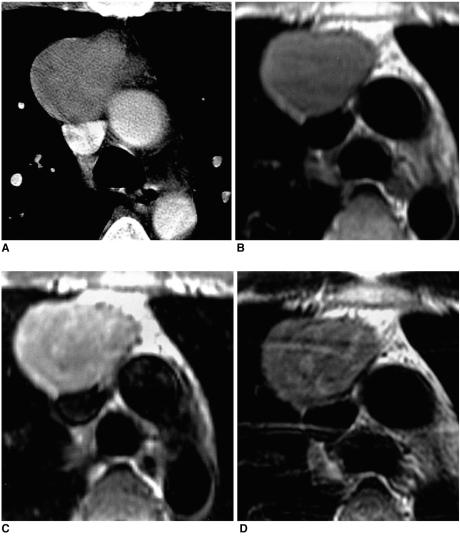

Thymic epithelial tumor is a distinctive pathologic entity exhibiting variable histologic features and heterogeneous oncologic behavior. Among the various classification systems, that of the World Health Organization has been adopted because of good correlation between histologic appearance and oncologic behavior. Radiologically, a smooth contour and round shape are most suggestive of a type-A tumor, whereas an irregular contour most strongly suggests type C. Pleural seeding is rare in type-A and AB tumors; calcification is suggestive of type B. Type-C tumors are significantly larger and more commonly associated with lymphadenopathy than type B3. At T2-weighted MR imaging, lobular internal architecture is more prominent in types B1, B2, and B3 tumors than in others. However, imaging findings among the various types overlap to some extent, and the ability of imaging studies to differentiate types AB, B1, B2, and B3 is limited.